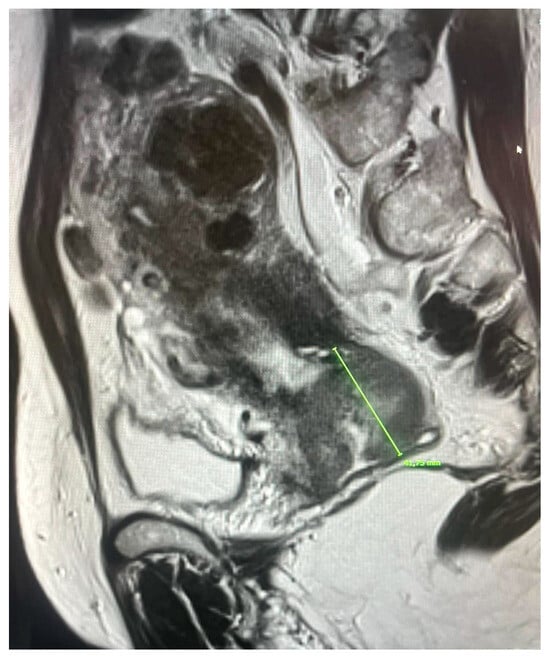

3.3. Stage IIIA–Extension to the Lower Third of the Vagina

In the 2018 FIGO classification, lower vaginal third involvement defines stage IIIA and leads to a worsening prognosis, as well as a notable change in treatment planning. Correct identification of this condition is therefore crucial to avoid staging errors and appropriately plan treatment.

Traditional clinical examination and transvaginal ultrasound have shown limitations in terms of sensitivity and specificity, especially in cases of bulky tumors or in the presence of bleeding. Multiparametric MRI, thanks to the tissue contrast of T2-weighted sequences, has proven superior. Under normal conditions, the vaginal wall appears as a thin, hypointense line on T2, separating the mucosa from the surrounding environment. Its loss or interruption is the key sign of tumor infiltration [30,31]. However, this finding can be distorted by inflammatory processes or motion artifacts, which is why integration with functional sequences is now considered essential.

Prospective studies have confirmed the accuracy of this method. Pálsdóttir et al. (2021) reported a specificity of 96% and a higher overall accuracy compared to transvaginal ultrasound (96% vs. 83%) [23]. Similarly, Zhu et al. (2021) showed that MRI achieves a specificity of 92%, compared to 80% for ultrasound, with a significant advantage in tumors that diffusely infiltrate the vaginal wall [22].

Other methods have also been compared with MRI. Vaginosonography, studied by Vidal Urbinati et al. (2022), showed a sensitivity and specificity of around 89%, demonstrating a fair degree of accuracy especially in small tumors [37]; however, MRI maintained an advantage in bulky cases, where ultrasound assessment is more complex.

The literature agrees that mpMRI is the reference technique for assessing vaginal extension, both for its ability to distinguish lower third involvement (crucial for staging) and for its ability to precisely define the length and volume of the disease. This information is essential not only for staging purposes but also for brachytherapy planning, where accurate delineation of the vaginal extension allows for more precise design of target volumes. Clinically, involvement of the lower third of the vagina leads to caudal extension of external beam radiation fields, potentially impacting late-stage morbidity, particularly sexual functioning and quality of life. Accurate assessment of vaginal extension is therefore essential not only for correct staging but also for adequate treatment planning.

Functional sequences may further contribute. Specifically, DWI has been proposed to increase sensitivity in cases where T2 assessment is uncertain, while DCE may provide clues to infiltration based on an early mucosal enhancement pattern. These parameters, although not yet fully validated on a large scale, could contribute to further improving diagnostic accuracy in the future.

In conclusion, MRI represents the most reliable method for assessing vaginal extension, with superior performance compared to transvaginal ultrasound and vaginosonography, and with a direct impact on correct staging and treatment planning (Figure 3).